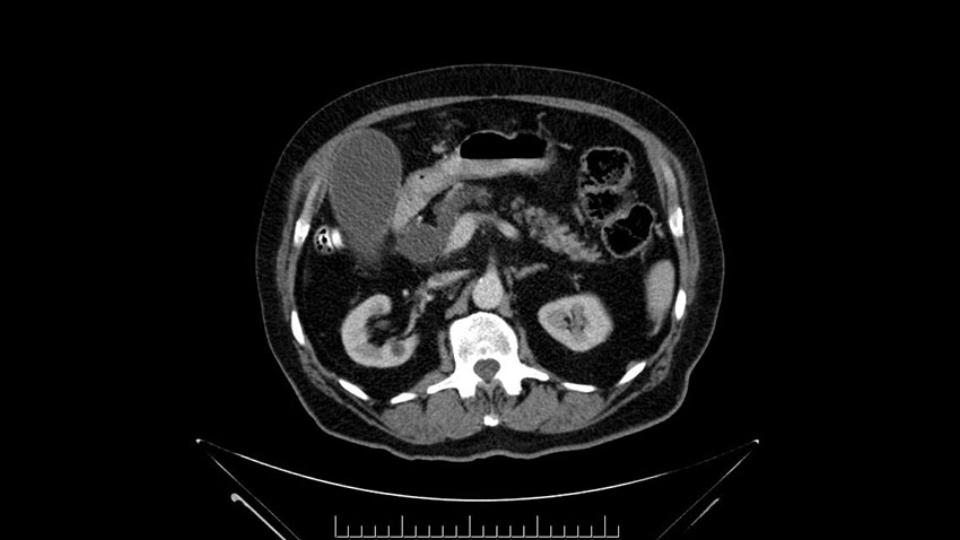

Then you look for anomalies. The one you worry about the most doing a Whipple is a replaced or aberrant right hepatic artery coming off the SMA at its origin. So again, find the SMA. You can find it because the renal vein goes through it. Follow it up, up-up-up. Nothing coming off of there that I can see here. Nothing coming off of it, nothing coming off of it and just to confirm it, look at the celiac trfurcation. There’s the celiac, there’s the bifurcation, there's the splenic artery, hepatic artery. Make sure there’s a right, which there is here. The right usually goes under the bile duct: important when you’re going around the bile duct to do a Whipple. A replaced right goes under the portal vein and the bile duct way over here on the right. That’s about it.

To plan a pancreatoduodenectomy, we start by reviewing the vascular anatomy, especially the origin of the celiac trunk, here, in front of the aorta, looking for any evidence of stenosis. In addition, we look at the origin of the superior mesenteric artery, to look for any branches, and any replaced right hepatic arteries coming from the superior mesenteric artery; which does occur in about 12% of the population.

Important points to keep in mind during a pancreatoduodenectomy:

First, the stenosis of the celiac trunk, which can be caused by arteriosclerosis, especially in a patient who is 83, or in patients who have arcuate ligament; we do see it, sometimes in much younger patients. In those cases, it may be that the circulation of the hepatic artery comes entirely from the gastroduodenal artery and its anastomoses, through the pancreaticoduodenal arteries, coming from the superior mesenteric artery. This means that before the gastroduodenal artery is ligated, we first clamp and wait 30 seconds to a minute, to feel and check the arterial inflow to the liver. If the pulse is diminished or there is a complete absence of the pulse, the surgery should be modified or probably a pancreatoduodenectomy cannot be done, because of the risk - when ligating the gastroduodenal artery - of causing fulminant hepatic ischemia postoperatively.

The second point about the vascular anatomy-, is to again look for right hepatic arteries in the hilum, coming from the superior mesenteric artery by palpating-through the Winslow Hiatus. Usually we will check for a pulse in the posterior aspect of the hepatic hilum, where a right hepatic artery should not usually be found. In this case, the precaution is to avoid an accidental ligation of the right hepatic artery that might jeopardize perfusion of the right lobe, or if there is a completely replaced hepatic artery that can put the liver circulation at risk.

The next thing we always evaluate, although we do not expect invasion to the portal veins in this case, we must always trace the path of the portal vein, in both directions, from top to bottom. The splenoportal confluence and the superior mesenteric vein, which in this case does not appear to be compromised.